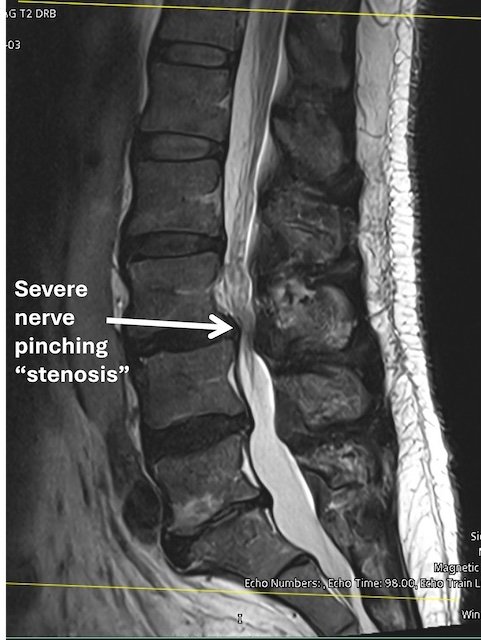

MRI scan showing severe nerve pinching or stenosis in the lumbar spine.

• MRI confirms spinal stenosis compressing the nerves